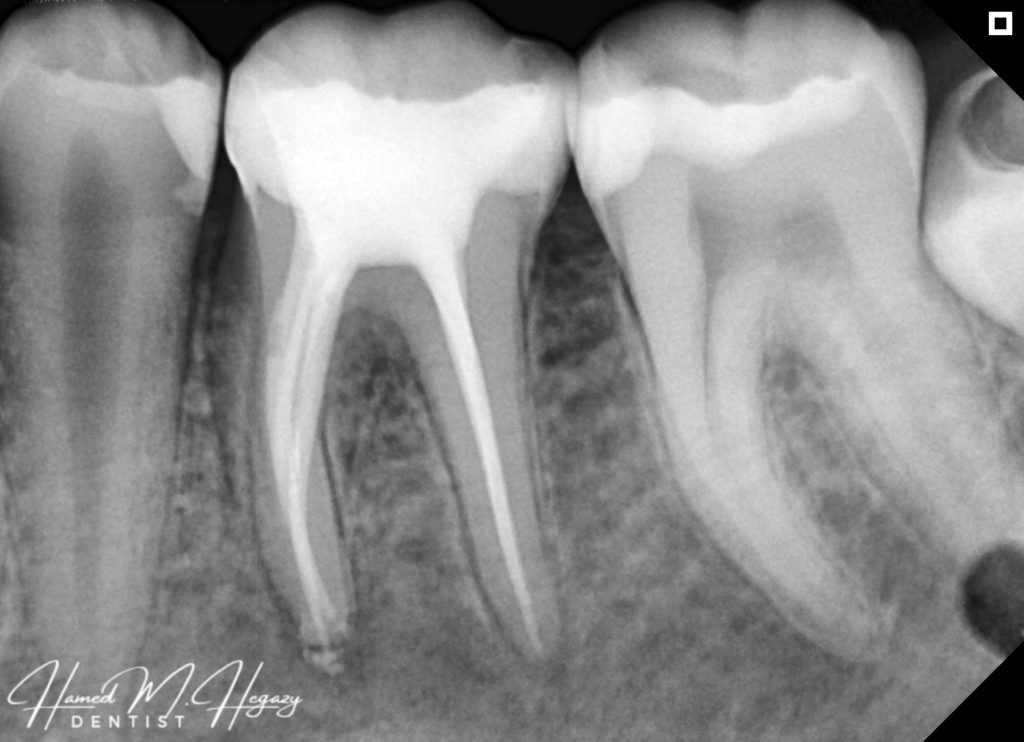

Obturation 1

Obturation and cavity design

Radiographic X-ray tell you every thing